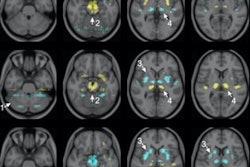

The researchers assigned 27 participants to receive focused ultrasound, while 13 others underwent a sham delivery procedure. The focused ultrasound was targeted onto the subthalamic nucleus in the patients' brains, on the side opposite to their main motor signs. The subthalamic nucleus is the neurosurgical target usually used for deep-brain stimulation treatments. In this trial, focused ultrasound was used instead to create the therapeutic lesions.

The study assessed participants' motor symptoms before and after the procedure on a scale of 1-44 (using the Movement Disorder Society-Unified Parkinson's Disease Rating Scale motor score), with higher scores indicating greater impairment. In the group treated with focused ultrasound, the mean score for the more affected side decreased from 19.9 at baseline to 9.9 at four months. In the control group, the score changed from 18.7 to 17.1.